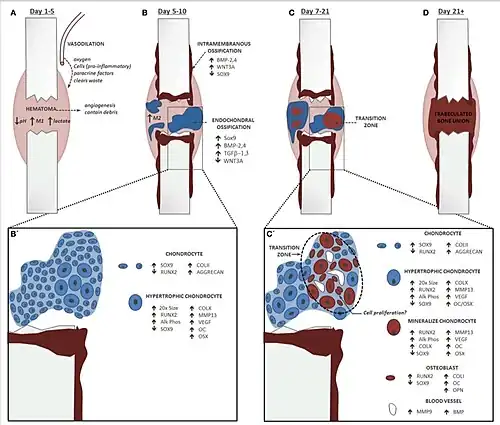

Fracture healing

For complete recovery of a fractured bone’s biomechanical functionality, the bone healing process needs to culminate in the formation of lamellar bone at the fracture site to withstand the same forces and stresses it did before the fracture. Indirect fracture healing, the most common type of bone repair,[10] relies heavily on endochondral ossification. In this type of healing, endochondral ossification occurs within the fracture gap and external to the periosteum. In contrast, intramembranous ossification takes place directly beneath the periosteum, adjacent to the broken bone’s ends.[10][12]